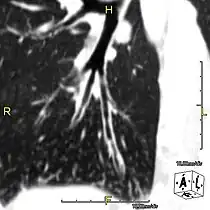

- CT image showing dilated and thickened medium-sized airways (bronchiectasis) in a patient with Kartagener syndrome